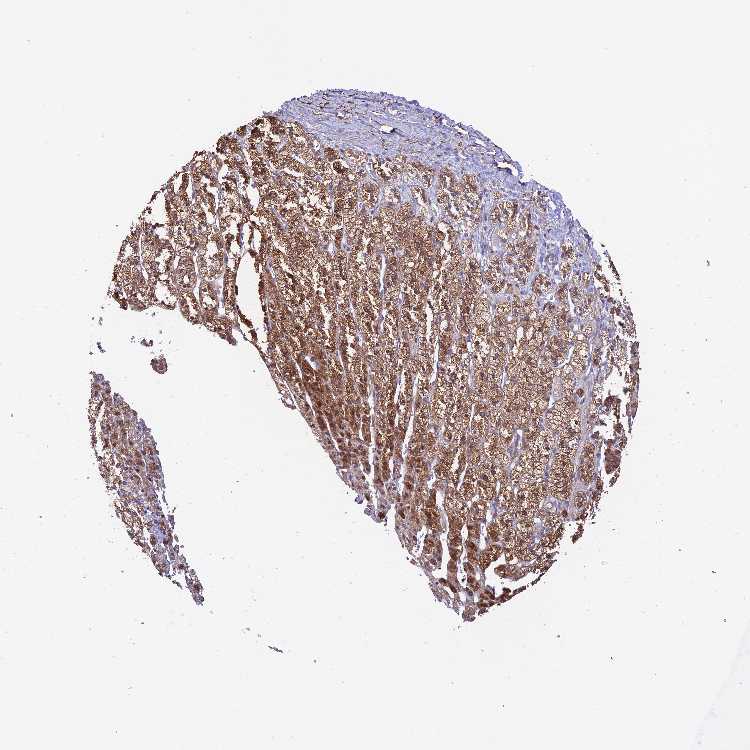

ADRENAL GLAND - Antibody stainingi

Antibody staining in the annotated cell types in the current human tissue is reported as not detected, low, medium, or high, based on conventional immunohistochemistry profiling in selected tissues. This score is based on the combination of the staining intensity and fraction of stained cells.

Each image is clickable and will lead to virtual microscopy that enables deeper exploration of all samples and also displays staining intensity scores, fraction scores and subcellular localization as well as patient and tissue information for each sample.

Antibody HPA044819

Glandular cells High